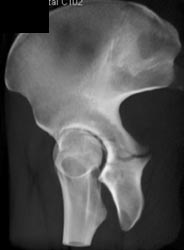

Acetabular Fracture